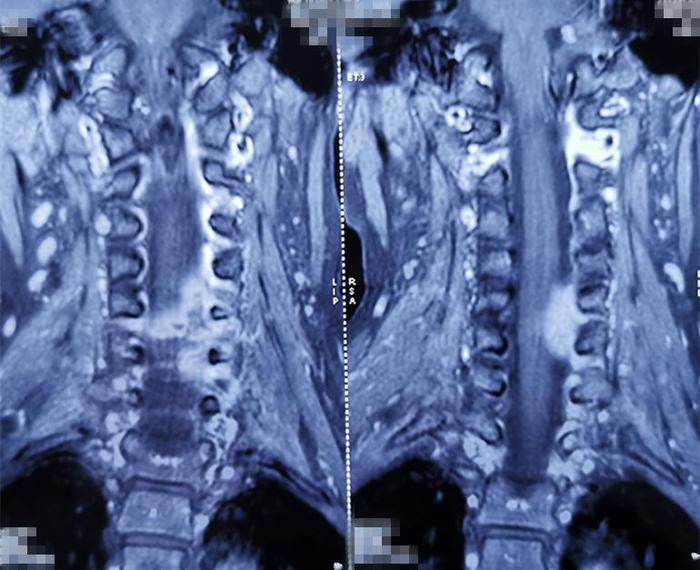

现病史:患者1年前在无明显诱因出现颈背部疼痛,呈间歇性发作,休息后可缓解,活动后加重。就诊于当地医院,行颈椎MRI检查,考虑颈椎嗜酸性肉芽肿可能,给予口服药物治疗,效果欠佳。约1个月前,患者自诉上述症状加重,并伴有左上肢放散痛,以上臂为主。门诊再次行颈椎MRI检查示,颈5椎体局部骨质破坏,颈4-6椎体左后方椎旁、椎管内脓肿形成;考虑结核可能性大。并影像学资料对比发现,颈5椎体骨质破坏较前加重伴椎管内脓肿、压迫神经脊髓。

术前影像学资料: